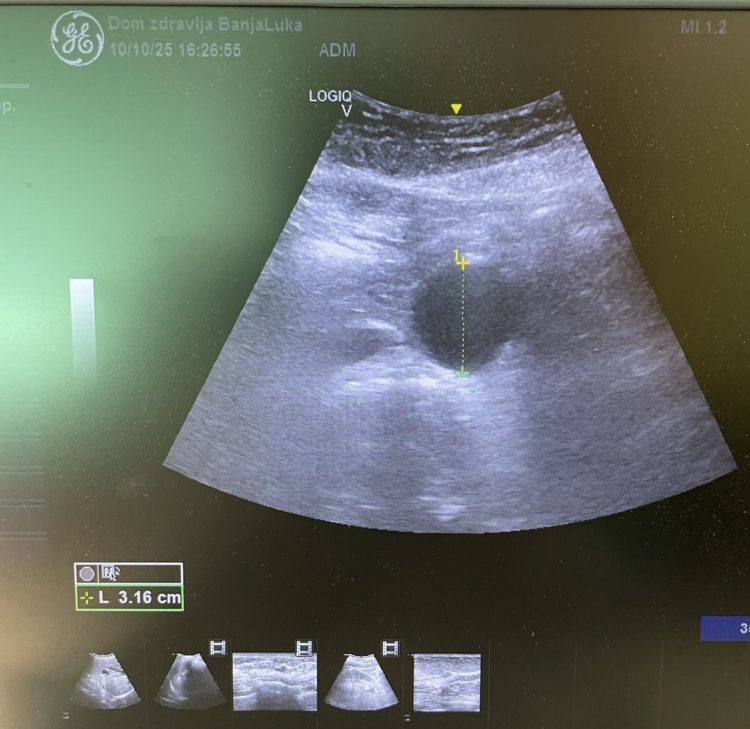

Tačno je mjesec dana od početka ultrazvučnog skrininga aneurizme abdominalne aorte, koji se u Domu zdravlja Banja Luka realizuje u saradnji sa međunarodnom organizacijom WINFOCUS i već bilježimo izuzetno važne rezultate: kod 7 pacijenata otkrivena je aneurizma, potencijalno životno ugrožavajuće stanje koje najčešće ne daje simptome.

Aneurizma abdominalne aorte često se razvija tiho, bez simptoma, a njena ruptura nosi visoku smrtnost. Zahvaljujući ovom preventivnom programu, naši doktori su u prvih mjesec dana uspjeli da identifikuju 7 slučajeva i tako omoguće pravovremeno liječenje i dalje praćenje ovih pacijenata.